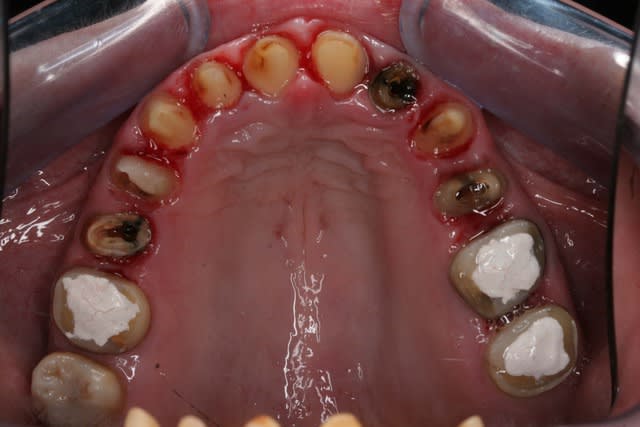

Voila la suite pour le maxillaire, le wax est fait sur arti en fonction de l'OIM obtenue après ortho. seule la 27 restera intacte.

Préparation des molaires pour permettre des RTE sous digue à travers les provisoires, retrait des anciennes couronnes et ancrages sur les 12, 15 et 25 endo satisfaisantes (couronnes ayant plus de 30 ans pour certaines!!!.

Tailles parallèles pour zircone 13 à 23 seront solidarisées pour éviter une migration post ortho.

Gingivectomie légère à la fraise à biseau pour harmoniser les collets, mais l'ortho a permis d'énormément faciliter ce travail.